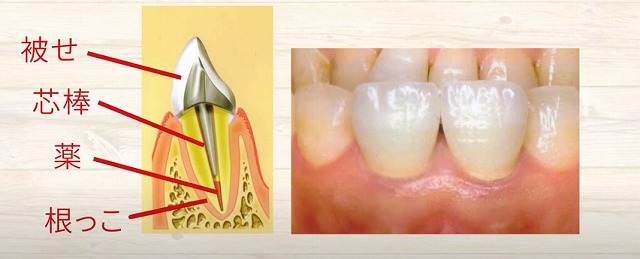

断面で見ていきますと、

骨の中に根っこが植わっており中が空洞になります。

空洞になっていますといろいろなものが

入ってきたりしますので、

入ってこないように根っこの中にお薬を入れます

そして被せをしようとしますが安定しません。

ですのでこのようなこのような杭みたいなものをつくり

この杭を穴の中に差し込みます

そうすると、この頭部分が出てきますから

これを土台にして帽子を被せる

というような治療を受けられています。

歯の根っこがあって、

その神経血管が元々あったところに

人工のお薬、そして芯棒、そして被せ

このように一直線上に入るわけです。

そして

根っこと

被せモノが

段差なく移行的に入るように被せ物をされます。

これをレントゲンで撮影すると、ある患者さんの写真ですが、

歯の根っこ

薬を詰めている部分

芯棒

被せモノ

歯の根っこの周囲は

白い骨で覆われている

という風にイメージしていただくと

わかりやすいかもしれません